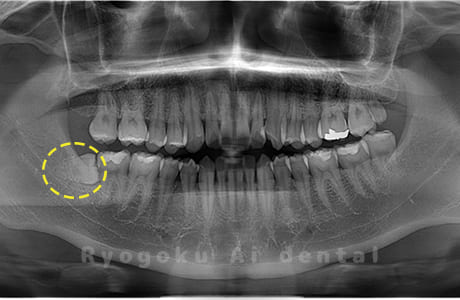

Case04

- 原因

- 上顎の親知らず、下顎の水平埋伏の親知らず

- 治療内容

- 上顎の親知らず、下顎の水平埋伏の親知らずを抜歯したケースです。

<リスク・副作用>

手術後は痛み、腫れ、痺れなどの副作用が生じる場合があります。